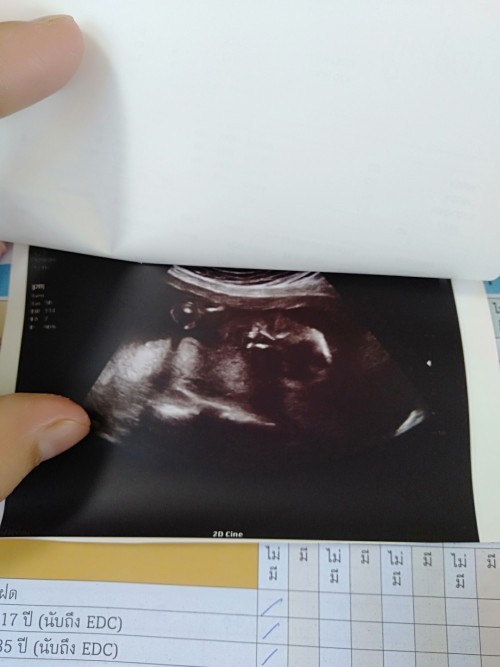

17wkแล้วคะ คลอด24มค64 ผชฮ๊าฟ